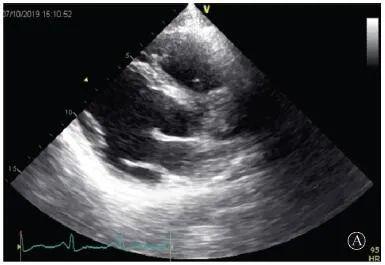

患者入院后無(wú)特殊不適,心率70次/min,血壓110/60 mmHg,心功能Ⅱ級(jí)。查血常規(guī):血紅蛋白139 g/L,白細(xì)胞7.39×109/L,血小板221×109/L。尿常規(guī)、便常規(guī)+潛血均正常。生化:丙氨酸氨基轉(zhuǎn)移酶38 U/L,白蛋白47 g/L,鉀3.9 mmol/L,肌酐(酶法)65 μmol/L,總膽固醇3.52 mmol/L,低密度脂蛋白膽固醇2.08 mmol/L。CK:1256→487 U/L,CK-MB 9.7→3.8 μg/L,cTnI 85.90→68.50 pg/ml。N末端B型利鈉肽原70 pg/ml。CK同工酶電泳:肌酸激酶MM質(zhì)量100.0%(此時(shí)CK-MB已正常)。血沉1 mm/第1小時(shí),高敏C反應(yīng)蛋白1.61 mg/L;補(bǔ)體:C3 0.876 g/L,C4 0.174 g/L。免疫球蛋白:IgG 9.52 g/L,IgA 1.73 g/L,IgM 0.62 g/L。血清蛋白電泳未見(jiàn)M蛋白。糖化血紅蛋白5.1%。乳酸(運(yùn)動(dòng)前)1.1 mmol/L,乳酸(運(yùn)動(dòng)中)6.6 mmol/L,乳酸(運(yùn)動(dòng)后)7.8 mmol/L。肌炎抗體譜:抗PM-SCL75(+),余均(-)。心電圖:aVL、V5、V6導(dǎo)聯(lián)T波倒置(圖2)。冠狀動(dòng)脈CT未見(jiàn)明顯異常。超聲心動(dòng)圖:左室舒張末內(nèi)徑55 mm,左室收縮功能減低,心尖部、左室壁普遍運(yùn)動(dòng)減低,以左室下后壁為著,左室下后壁肌小梁明顯增多可見(jiàn)隱窩,疏松層與致密層之比為1.7;左室射血分?jǐn)?shù)(雙平面)45%;右冠狀動(dòng)脈開(kāi)口6.5 mm,開(kāi)口處未見(jiàn)明確瘤樣擴(kuò)張(圖3)。

A:胸骨旁長(zhǎng)軸平面,左室舒張末內(nèi)徑略增大,室壁無(wú)明顯增厚;

圖3 患者入院后超聲心動(dòng)圖